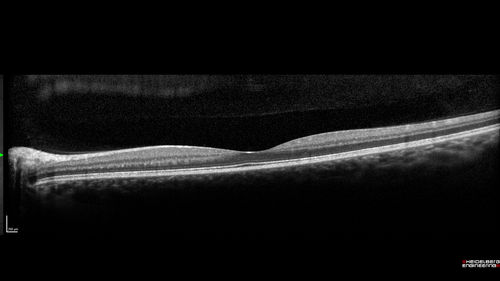

Cat Scratch - Neuroretinitis OD AND retinitis OS - Bartonella henselae positive

27 year old female with exposure to cats and prior fever.  Reports with recent vision loss right eye.  She was treated with doxycycline and within 2 weeks the right eye looks better.  Then she skipped all follow-up visits.  The right eye presented 20/200 and the left 20/16